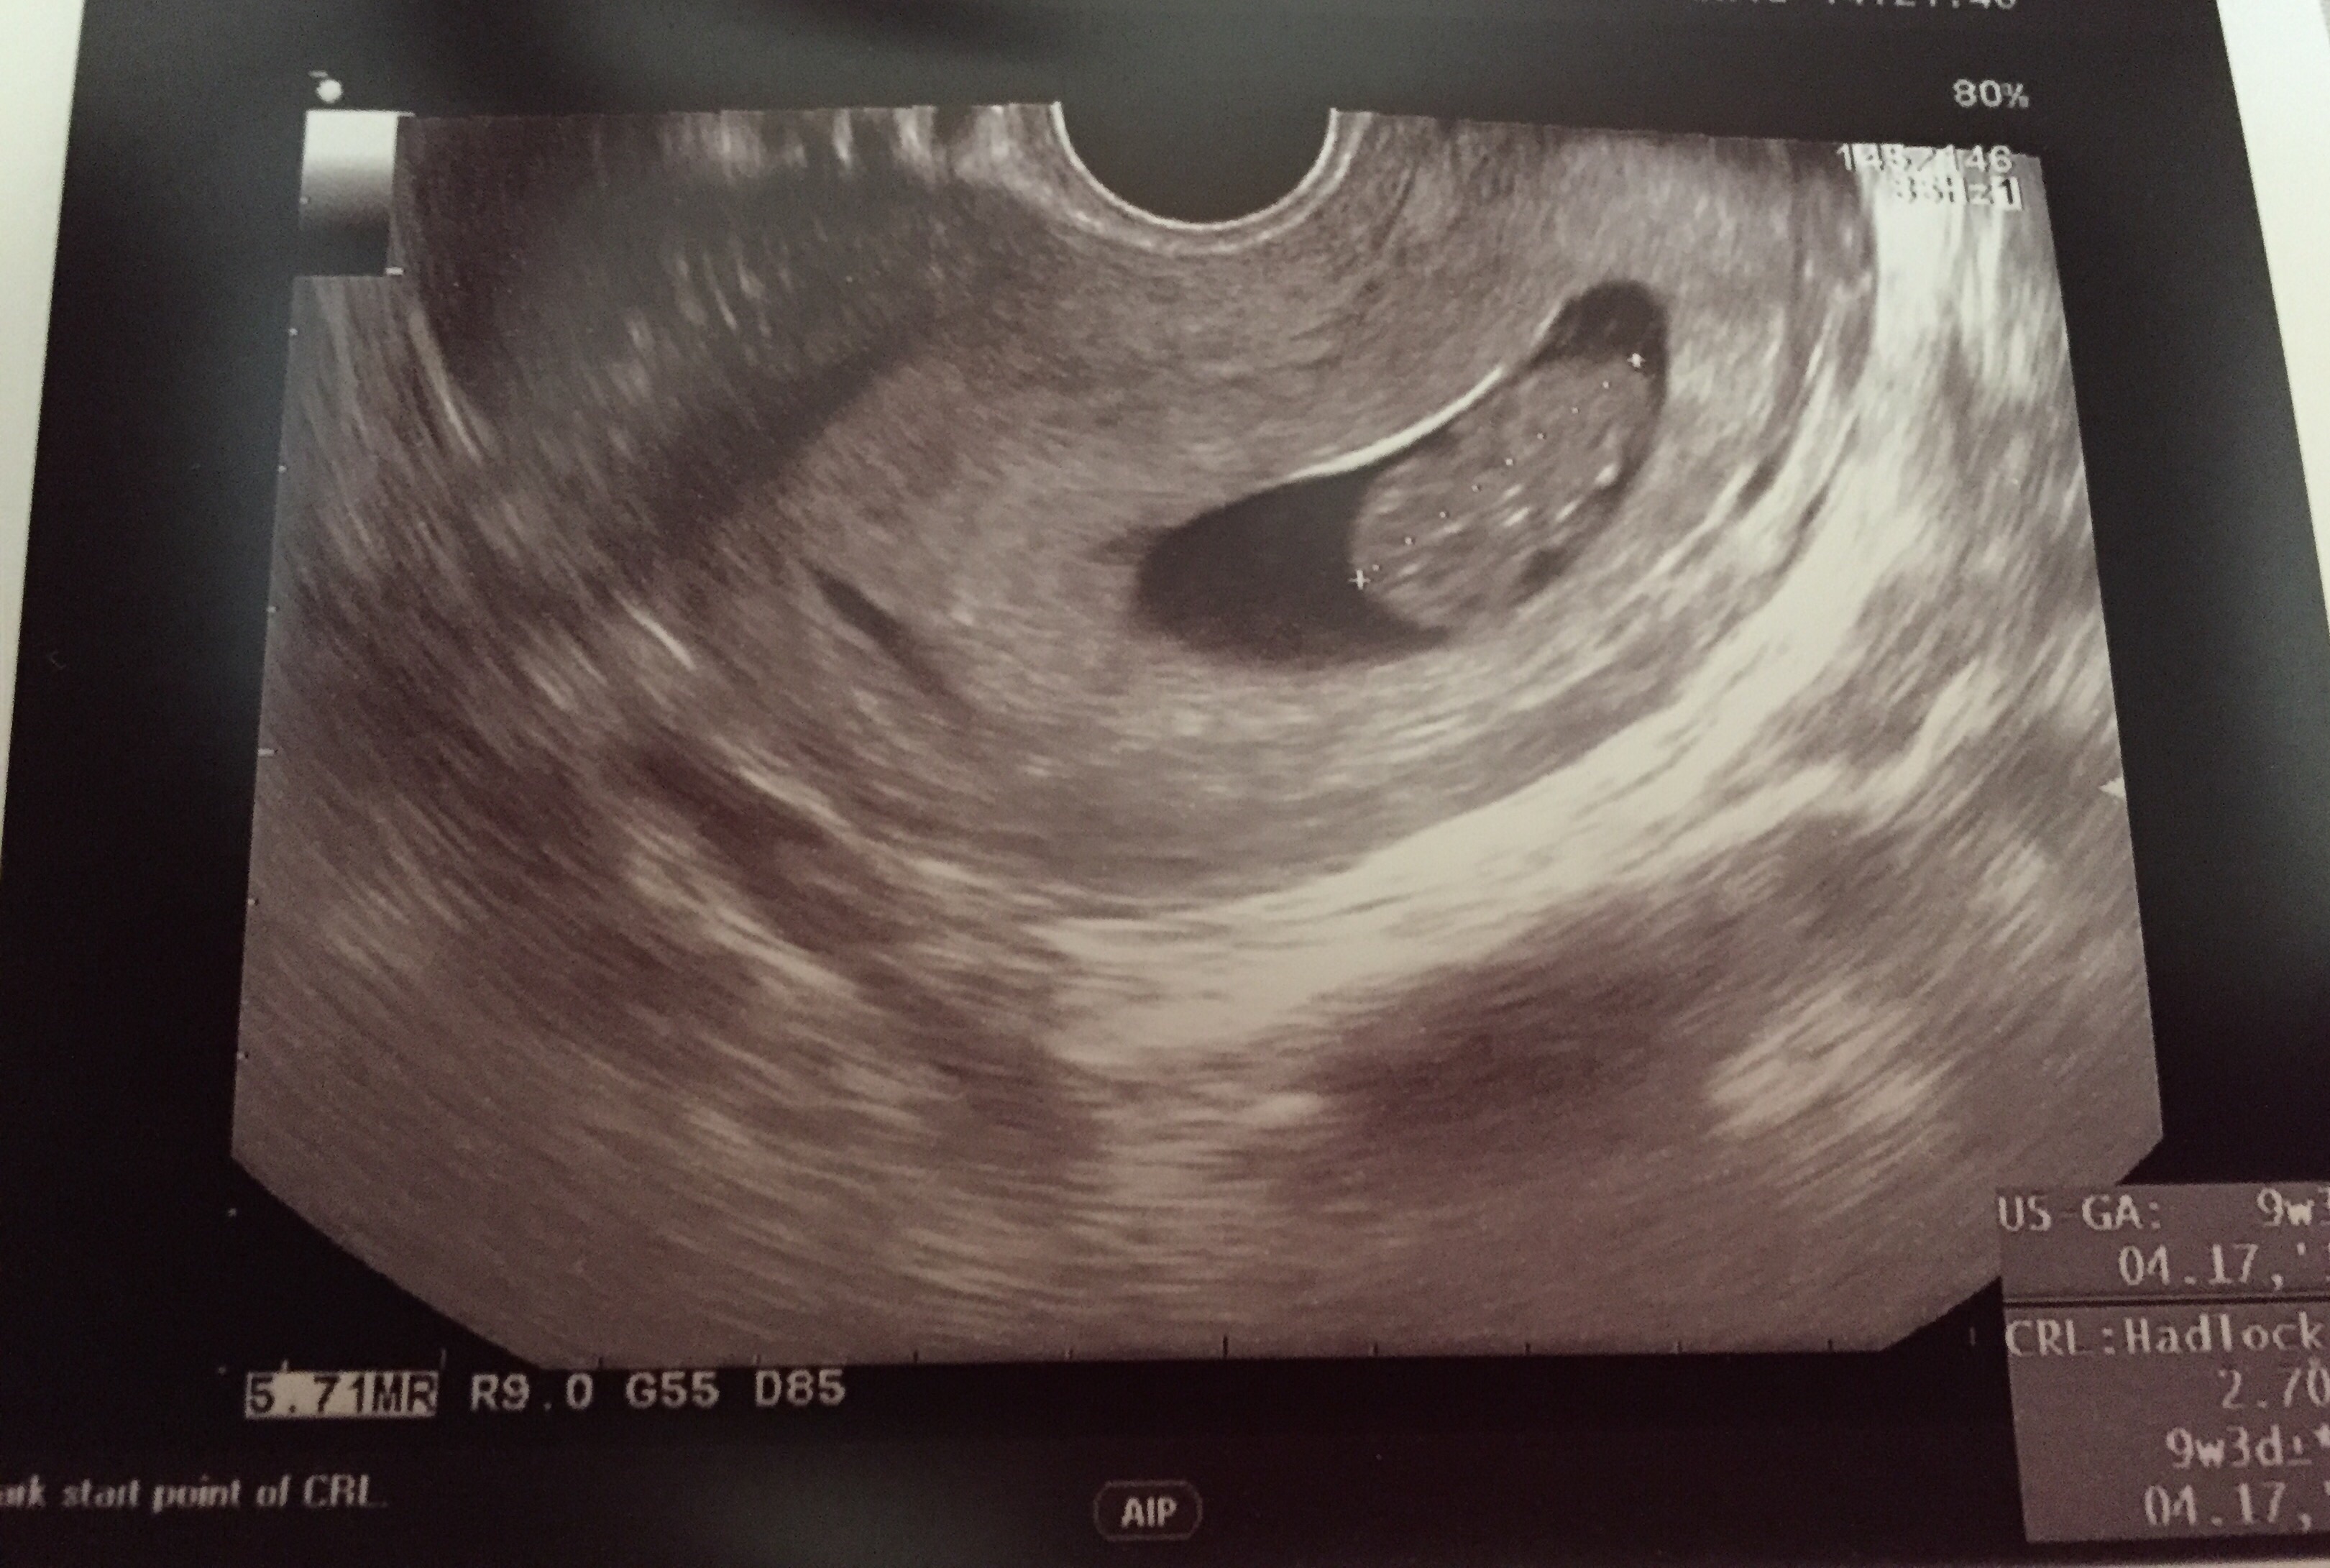

• 9weeks 2days. And I was not prepared for the all the emotions ❤️